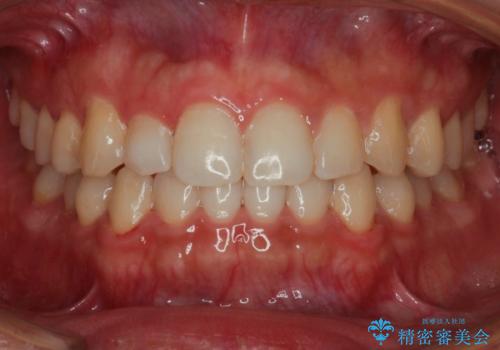

[ 非抜歯矯正 ] 歯を抜かずに出っ歯の治療

![[ 非抜歯矯正 ] 歯を抜かずに出っ歯の治療の症例 治療前](https://seimitsushinbi.jp/wp/wp-content/uploads/2025/03/IMG_6660-500x350.jpg?v=1741945892)

![[ 非抜歯矯正 ] 歯を抜かずに出っ歯の治療の症例 治療後](https://seimitsushinbi.jp/wp/wp-content/uploads/2025/03/IMG_7513-500x350.jpg?v=1741945816)